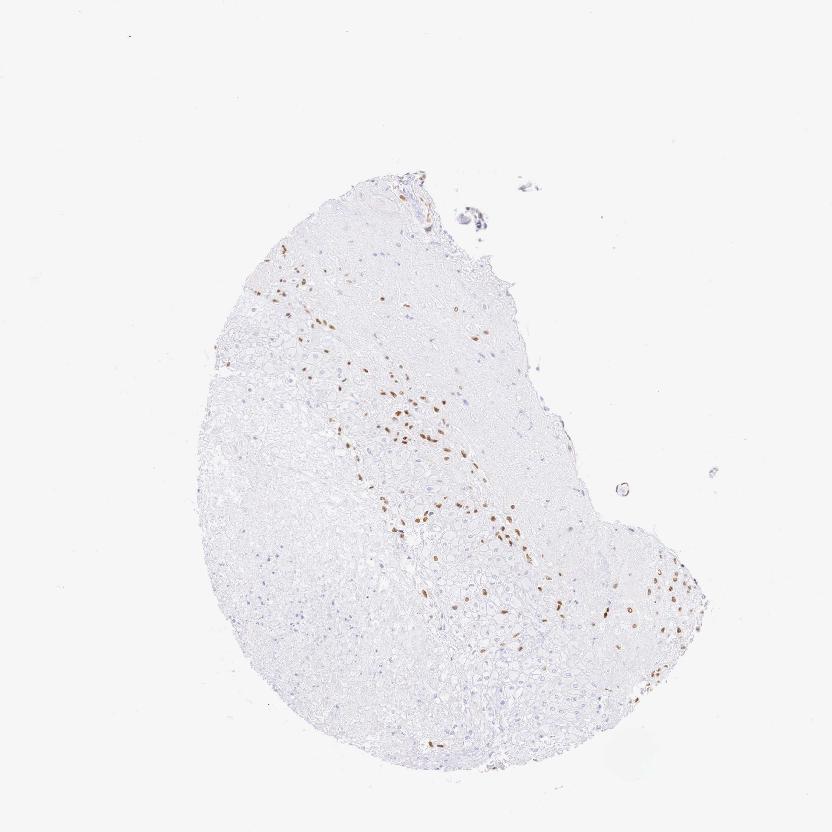

Antibody staining in the annotated cell types in the current human tissue is reported as not detected, low, medium, or high. This score is based on the staining intensity and fraction of stained cells.

Information about each individual sample is listed below, including gender, age, a tissue section image and estimated fractions of cell types. pTPM (transcripts per million) values give a quantification of the gene abundance which is comparable between different genes and samples.

Placenta sample 385 pTPM: 49.6

Cell types%

Trophoblastic cells: 50 Endothelial cells: 20 Other cell types: 30

Female, age 37

Placenta sample 398 pTPM: 39.5

Female, age 36

Placenta sample 413 pTPM: 28.5

Trophoblastic cells: 45 Endothelial cells: 10 Other cell types: 45